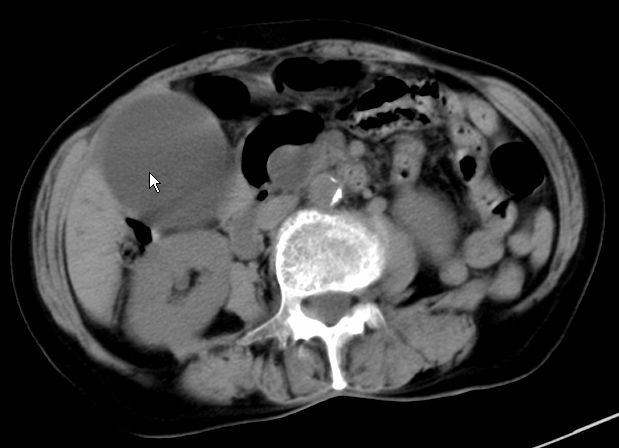

以下是引用zjzjr在2008-12-16 12:49:00的发言:[br]肝内外胆管全程扩张,胆囊明显增大,未见占位征像.建议mrcp.

以下是引用jiangjing在2008-12-16 13:19:00的发言:[br]肝内外胆管全程扩张,胆囊明显增大,扩张胆总管下段径较中上段小,未见胰管扩张,提示胆总管远端梗阻伴感染.建议增强及mrcp 检查

以下是引用朱亮在2008-12-16 12:54:00的发言:[br]胆总管远端应薄层扫描 胆总管逐渐变细 考虑胆系慢性炎症